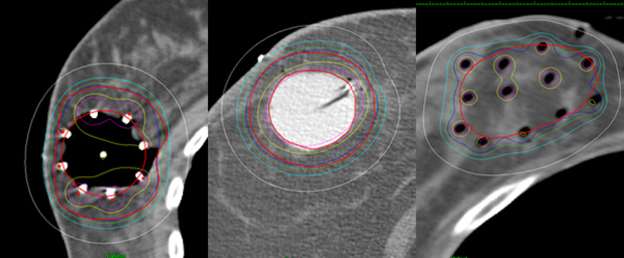

Textbook of Radiation Oncology: 9780721653365: Medicine & Health Science Books @ Amazon.com

Textbook of Radiation Oncology: 9780721653365: Medicine & Health Science Books @ Amazon.com,

Textbook of Radiation Oncology: 9780721653365: Medicine & Health Science Books @ Amazon.com, Radiation Biology for Medical Physicists | C. S. Sureka, Christina Arm,

Radiation Biology for Medical Physicists | C. S. Sureka, Christina Arm, Breast Cancer - Radixact,

Breast Cancer - Radixact, Breast Cancer – Brachytherapy - Radiation Oncology | UCLA Health Jonsson Comprehensive Cancer Center,

Breast Cancer – Brachytherapy - Radiation Oncology | UCLA Health Jonsson Comprehensive Cancer Center, Radiation Oncologist Qualifications and Certification | Gray and White Law

Radiation Oncologist Qualifications and Certification | Gray and White Law